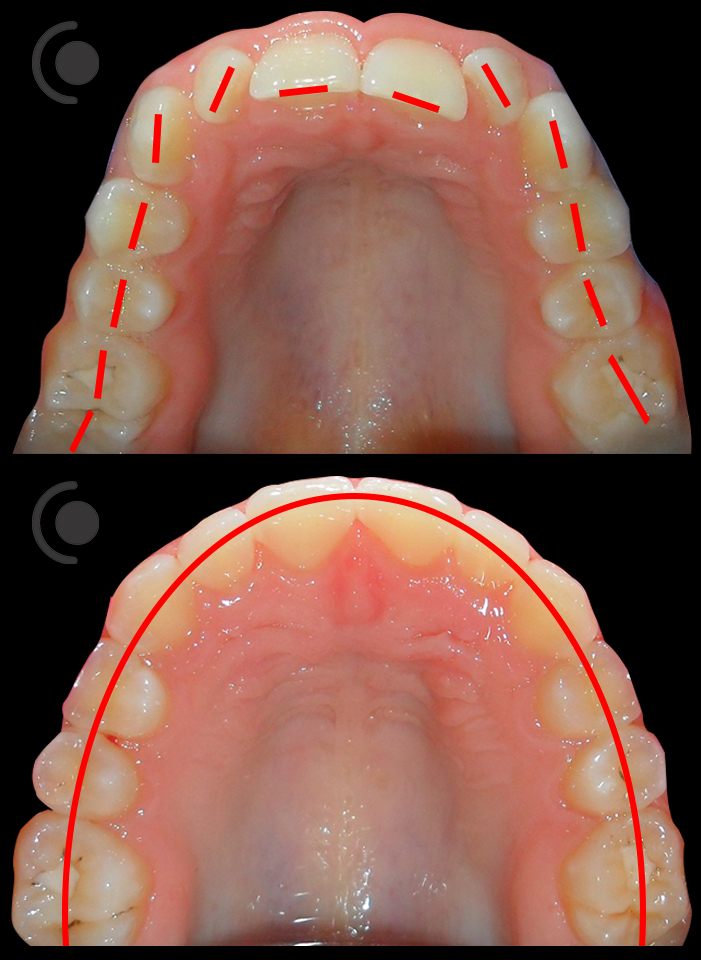

O našoj kvaliteti najbolje govore naši rezultati!